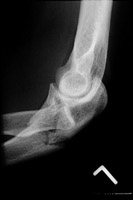

- Click on the image for a larger versionAAP radiograph of the elbow. This shows a comminuted fracture of the proximal ulna.